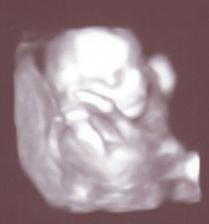

10.12.2007 - byli jsme na 3D ultrazvuku, máme asi 17 minutový záznam miminka a na 99% určené pohlaví (ale zatím je to TAJEM)

25.12.2007 - Tak už to není tajné ani tady na koníku, čekáme holčičku ;o)